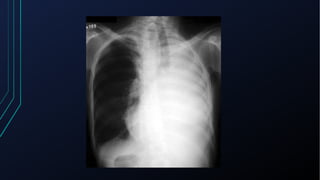

Laringe/Traquéia

• Pode estar deslocada em processos tumorais do pescoço e

mediastino e em doenças pulmonares (pneumotórax, derrames

pleurais, atelectasias)